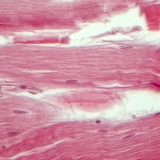

Tejido tendinoso (corte longitudinal)

magnificación de 400x